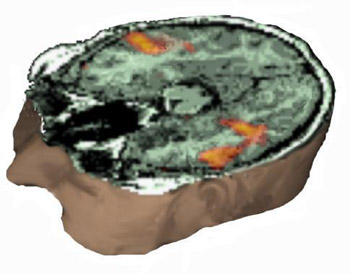

Triple Rendering: MRI (T1), MRI-FLAIR, and fMRI. Left-rostral-top view.

MRI of the head with partial exposure of the brain and skull. An axial view located at the superior third of the inferior frontal gyrus demonstrates in red the activation obtained with a verb generation task. The yellow spot represents the lesion and is derived from a fluid attenuated inversion recovery (FLAIR) sequence, and rendered with the rest of images, revealing the relationship between the lesion and the eloquent areas.